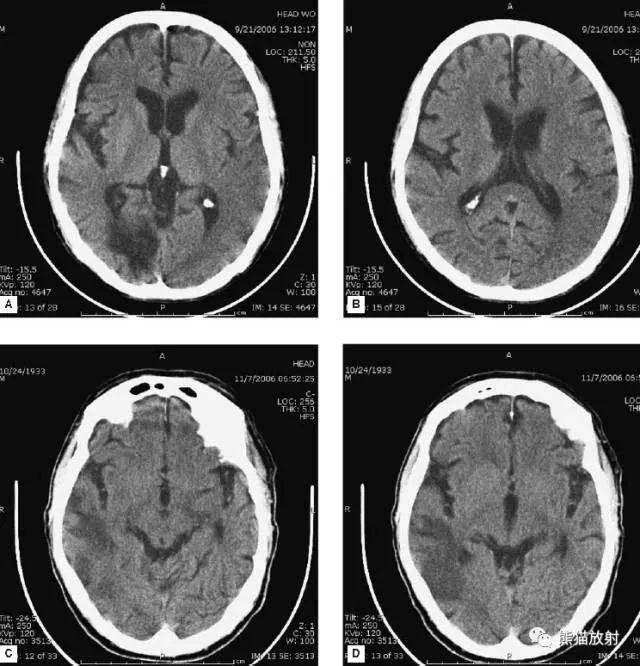

82岁脑出血后脑积水,北京某脑科医院治反致感染后19个月仍走路不稳